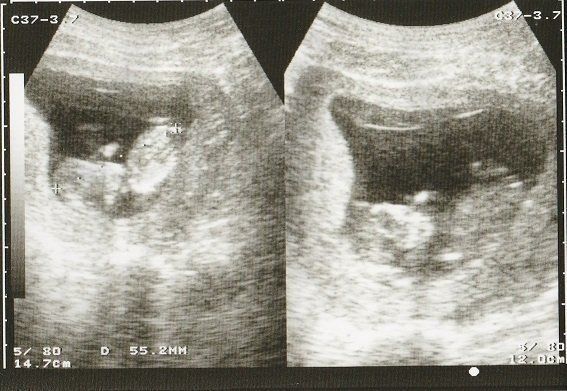

妊娠26週目のエコー写真 男の子であることが判明

左側のエコー画像に、男の子のシンボルが写っています。人によっては、生まれるまで男の子か女の子か告げて欲しくないという方もいらっしゃるようですが、私の場合、お医者さんに何も聞かれずに「男の子ですね」と言われました。

左側は頭の画像。赤ちゃんの頭もだいぶ大きくなりました。